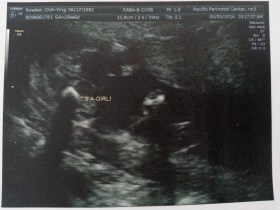

It’s a girl!

Just got the news. It’s a girl.